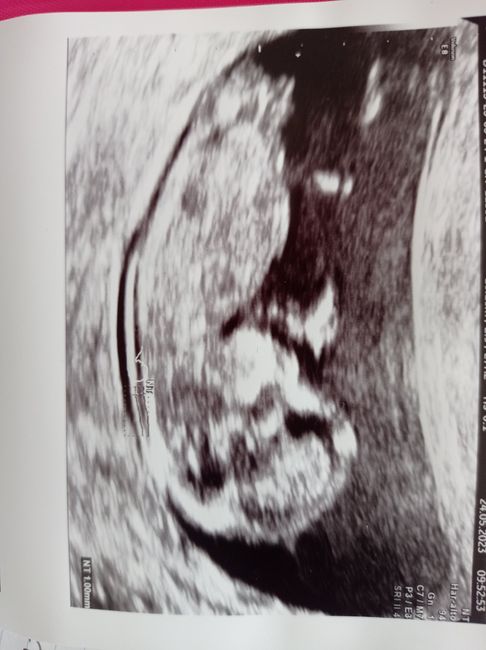

Ciao ragazze! Nell'attesa chi vuole giocare con me? Secondo voi è maschio o femmina? Fatta eco stamattina a 11+6! Io onestamente non saprei dire☺ ho letto la teoria Nub theory ma non riesco a interpretare la mia eco!